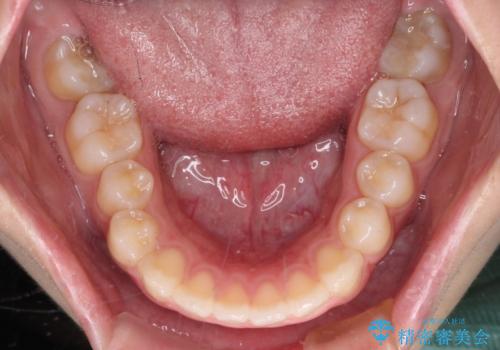

再矯正 開咬に後戻りした歯列をインビザラインで改善

- 矯正治療の後戻りを気にして来院された患者様です。

デコボコと上下前歯の隙間が気になるものの、しっかりと治療をしたいという意思はないとのことで、インビザラインの中でもアライナー数に制約のあるライトパッケージを用いて、治療できる範囲まで歯列を改善していくこととしました。

インビザラインは前歯部の開咬に効果的であることが多く、ライトパッケージにもかかわらず、十分満足のいく仕上がりとなりました。